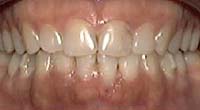

Treatment Time: 9 months

Aligners: 19 Lower